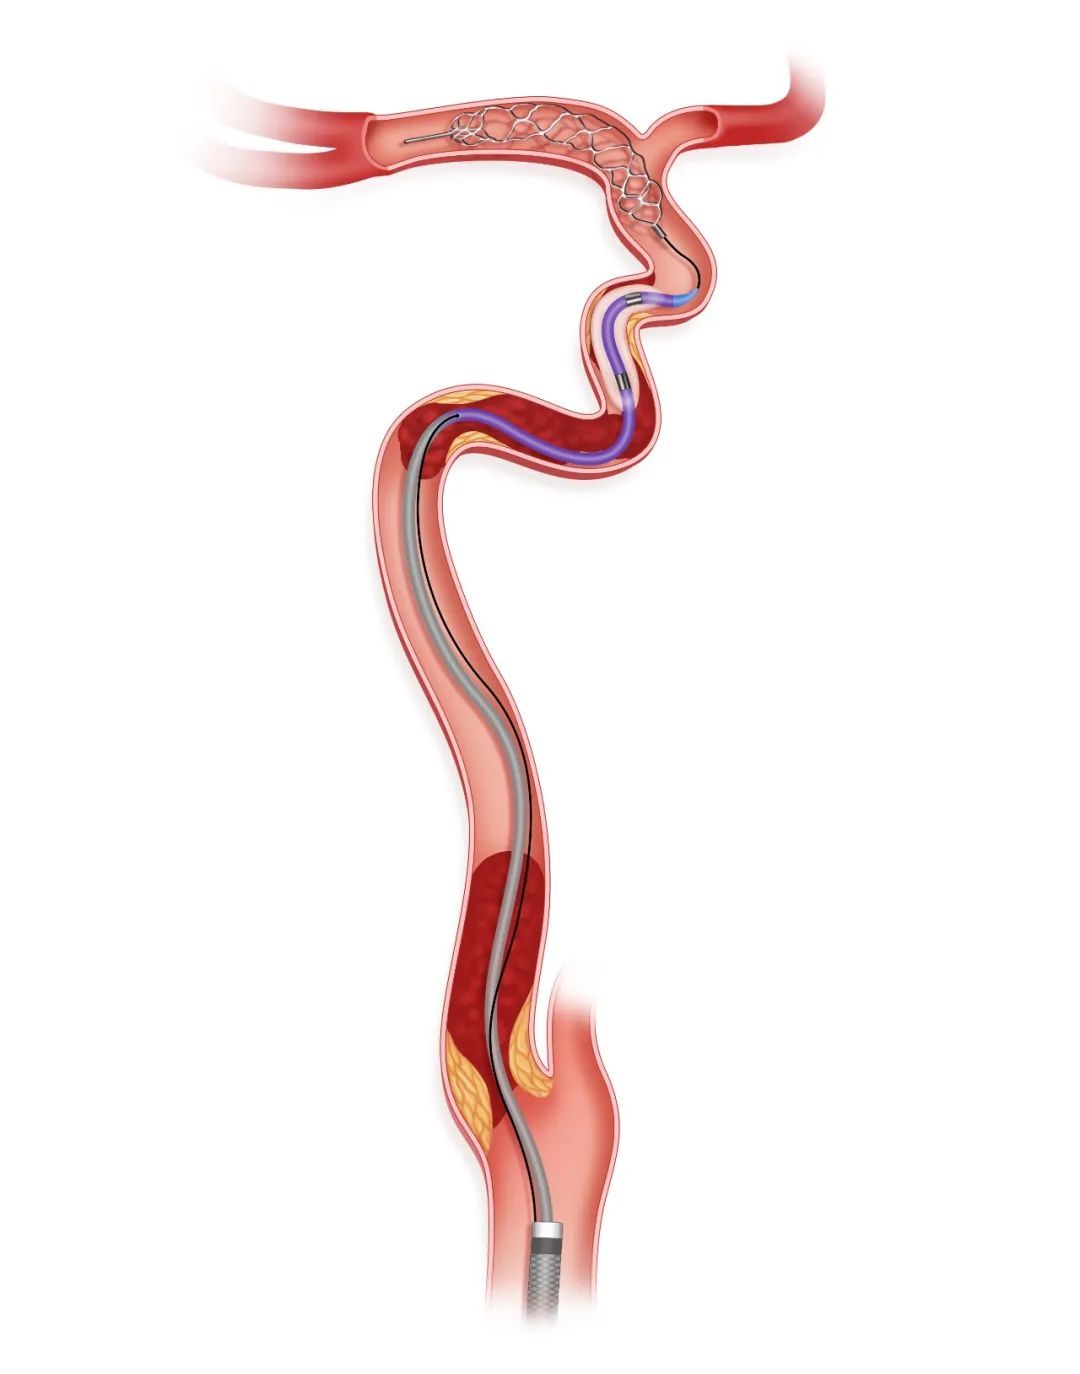

步骤三

SacSpeed®球囊扩张导管扩张后足量、足压力造影判断闭塞性质

沿Syphonet®取栓支架输送导丝送入小直径的SacSpeed®球囊扩张导管(2mm-2.5mm),由远及近依次对可疑病变部位进行扩张,后再次足量、足压力造影,明确闭塞段内原始病变部位、继发血栓部位和假性闭塞部位。